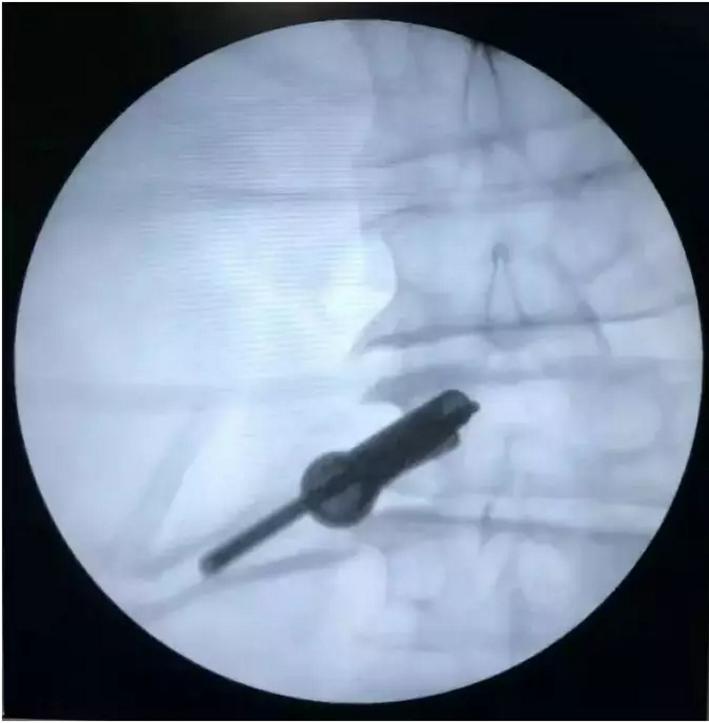

手术过程掠影

本次手术由张君副主任医师主刀,在黑光主治医师、谭可可主治医师及马莉护士长等人的配合下,顺利完成“(电动磨钻助力下)腰2-3椎间孔镜手术”——经皮穿刺椎间盘抽吸治疗术+低温等离子椎间盘射频消融术+脊髓和神经根粘连松解术。手术结束当时患者疼痛症状即完全消失,术后平卧24小时后患者佩戴腰围下床活动,疼痛症状未再出现,术后恢复良好。